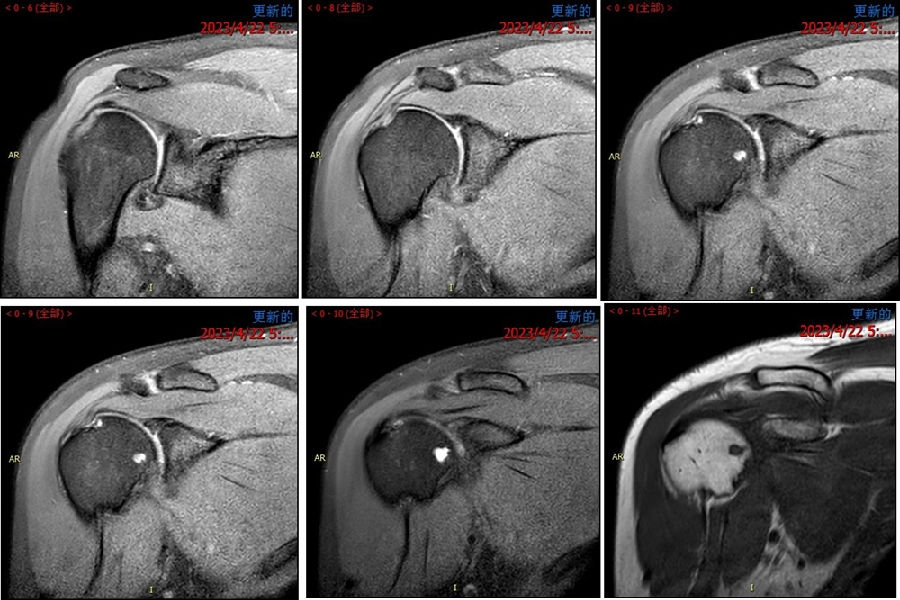

图 25-27 MRI

双侧CT三维扫描显示:健侧肩胛盂宽度D=25.9,患侧D=23.9,患侧肩胛盂骨性缺损d=6.2,骨性盂唇缺损面积d/D为23.9%(<25%)。肩胛盂轨迹GT(83%D-d)为15.3mm。

图28双侧CT三维扫描

图29 Hill-Sachs间隙为13.8mm(<15.3mm)

图30 评估结果

评估报告提示:右肩胛骨关节盂前下缘撕脱骨折,符合骨性bankart损伤。右肱骨头后上缘凹陷骨折,符合Hill-Sachs损伤。Hill-Sachs间隙为13.8mm(<15.3mm),为轨迹内肩关节前脱位。